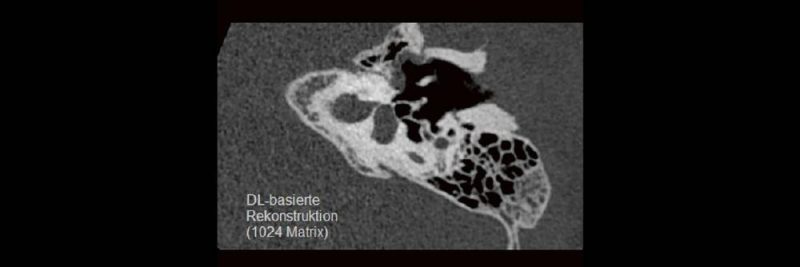

DEEP-LEARNING-REKONSTRUKTION IN DER NEURORADIOLOGIE

Die CT ist ein essentielles Routine-Verfahren in der Neuroradiologie. Bei steigender Bildqualität konnte die Röntgendosis mit neuen Technologien in der letzten Dekade deutlich gesenkt werden, was für die zielgerichtete und möglichst schonende Behandlung von Patienten von großer Bedeutung ist. Mit der Deep-Learning-Rekonstruktion steht ein neues Verfahren zur Verfügung, welches die Befunderhebung noch einmal deutlich verbessert. Technische Hintergründe und klinische Anwendungen im Rahmen der Neuroradiologie werden vorgestellt und diskutiert.

Im Vergleich zur Spiral-Computertomographie (SpCT) kann die Volumen-Computertomographie (VCT) hierbei Vorteile bieten. Mit der Verbesserung der auf künstlicher Intelligenz basierenden Rekonstruktionsalgorithmen kann nicht nur die Strahlendosis erheblich reduziert, sondern auch die diagnostische Aussagekraft erheblich verbessert werden. Technische Fortschritte mit Schwerpunkt auf KI-Algorithmen und deren umfangreiche klinische Anwendung werden vorgestellt und diskutiert.